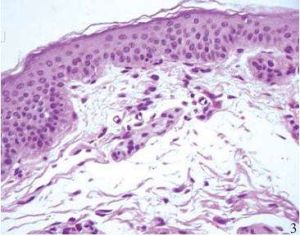

結締組織

組成。細胞有巨噬細胞、成纖維細胞、漿細胞、肥大細胞等。纖維包括膠原纖維...、巨噬細胞、漿細胞、肥大細胞、脂肪細胞、未分化的間充質細胞。此外,血液中...物質以及參與和調節人體免疫應答等功能。 疏鬆結締組織是由細胞 (1)趨化性...